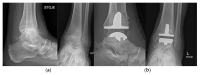

Osteoarthritis is a degenerative condition affecting the whole joint with the underlying bone, representing a major source of pain, disability, and socioeconomic cost worldwide. Age is considered the strongest risk factor, albeit abnormal biomechanics, morphology, congenital abnormality, deformity, malalignment, limb-length discrepancy, lifestyle, and injury may further increase the risk of the development and progression of osteoarthritis as well. Pain and loss of function are the main clinical features that lead to treatment. Although early manifestations of osteoarthritis are amenable to lifestyle modification, adequate pain management, and physical therapy, disease advancement frequently requires surgical treatment. The symptomatic progression of osteoarthritis with radiographical confirmation can be addressed either with arthroscopic interventions, (joint) preservation techniques, or bone fusion procedures, whereas (joint) replacement is preferentially reserved for severe and end-stage disease. The surgical treatment aims at alleviating pain and disability while restoring native biomechanics. Miscellaneous surgical techniques for addressing osteoarthritis exist. Advanced computer-integrated surgical concepts allow for patient personalization and optimization of surgical treatment. The scope of this article is to present an overview of the fundamentals of conventional surgical treatment options for osteoarthritis of the human skeleton, with emphasis on arthroscopy, preservation, arthrodesis, and replacement. Contemporary computer-assisted orthopaedic surgery concepts are further elucidated.